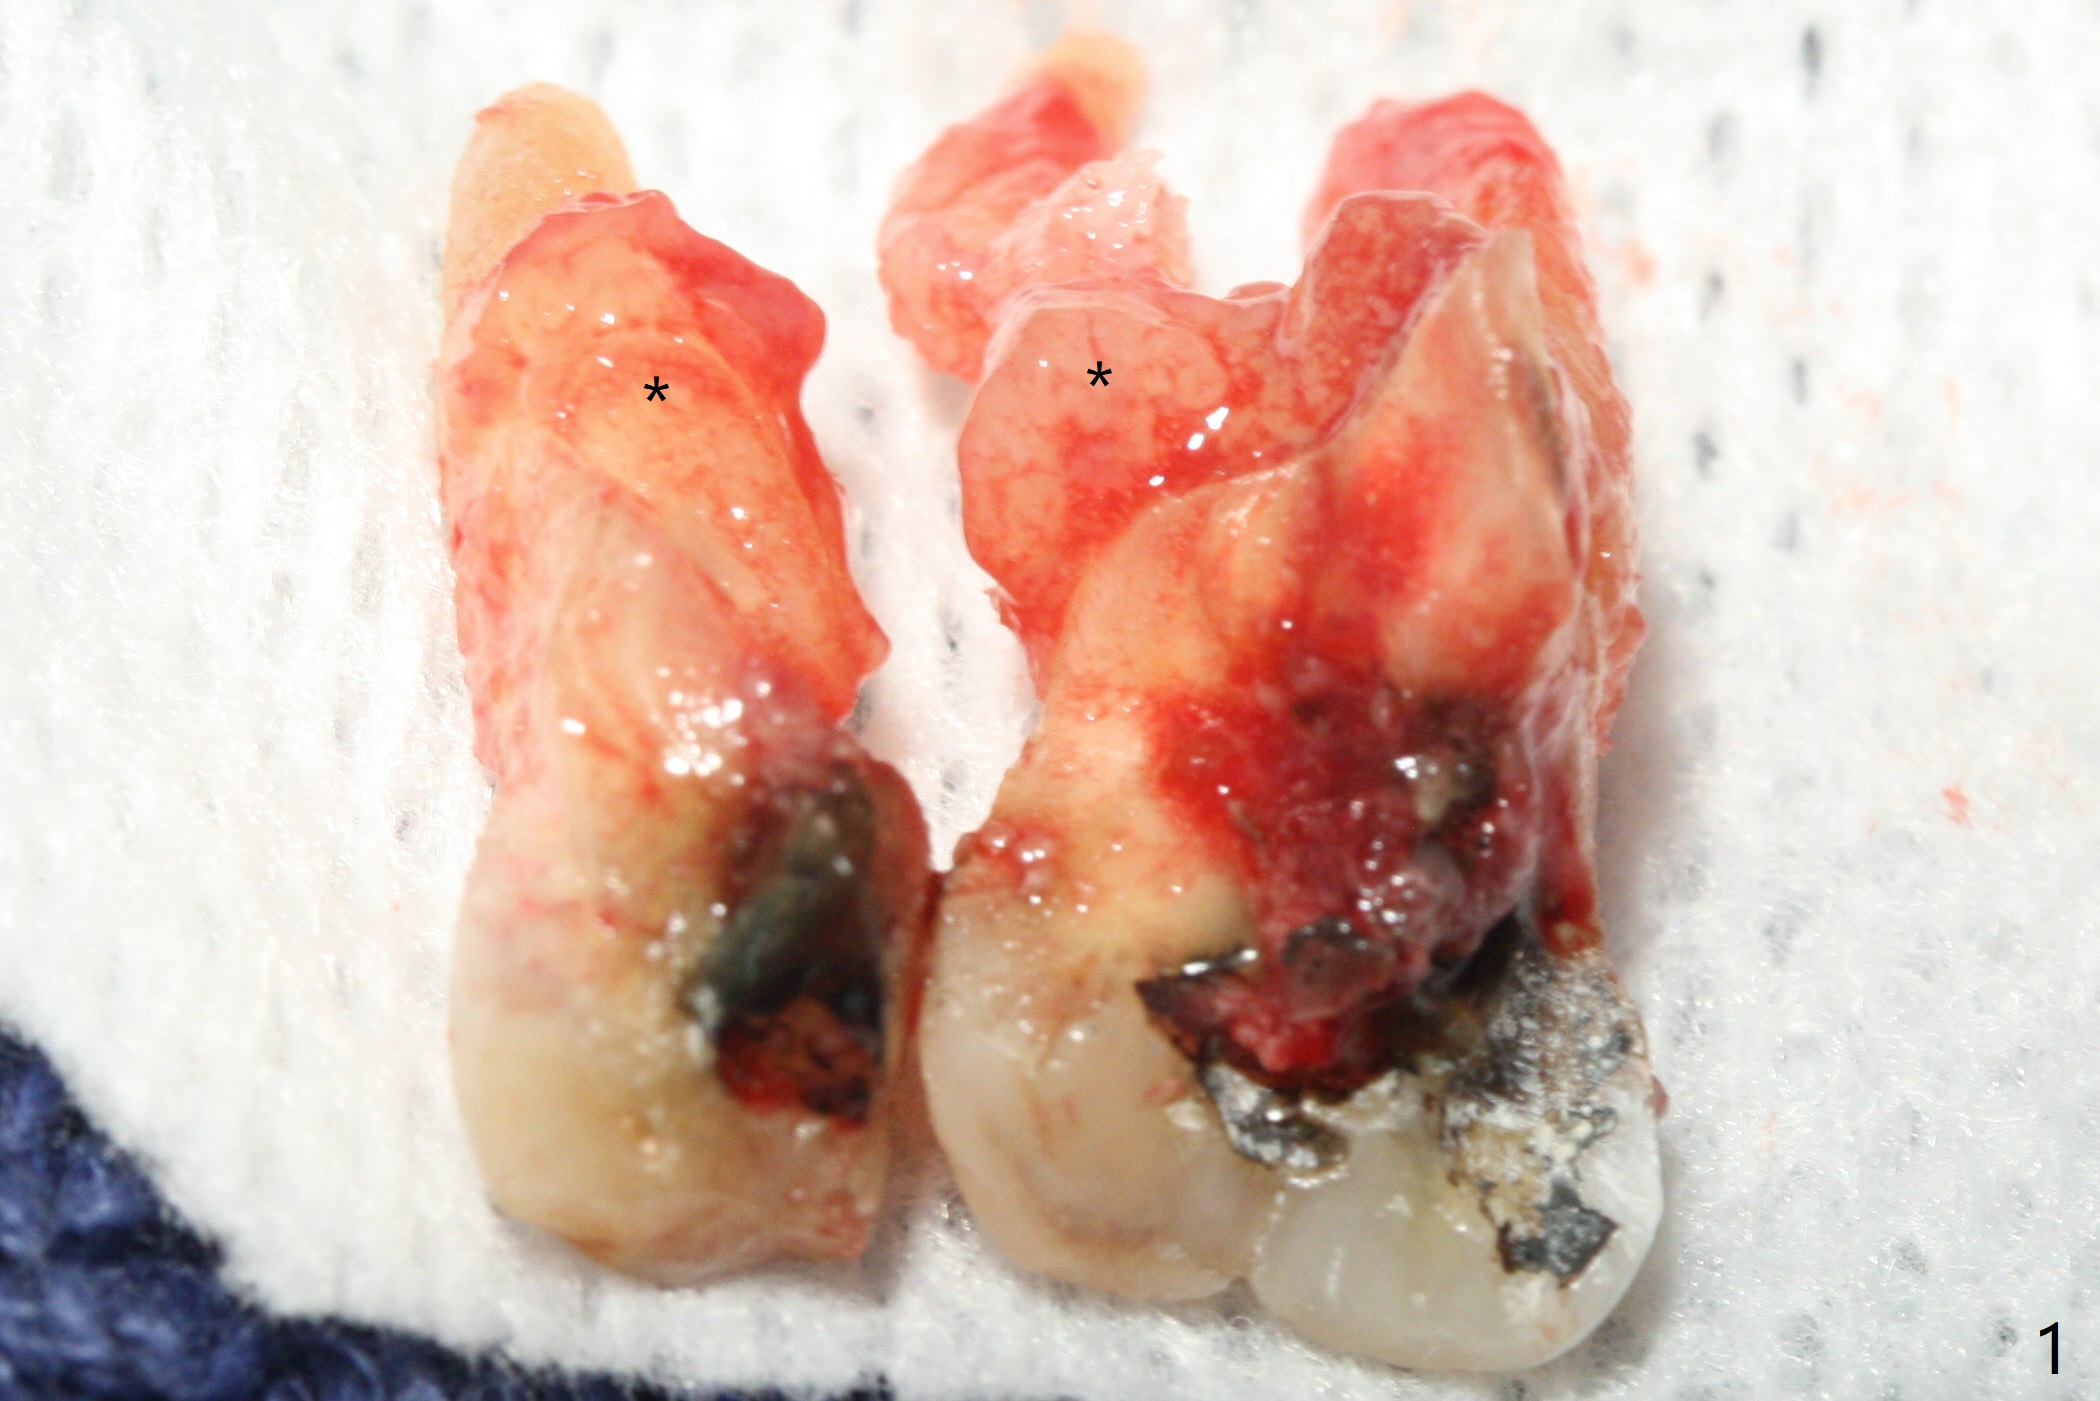

After removal of granulation tissue from the sockets associated with the fractured tooth at #14 (Fig.1 (* granulation tissue)) and initial osteotomy in the septum with a 2 mm drill for 8.5 mm, the sinus floor is penetrated by a parallel pin (Fig.2). But the sinus membrane remains intact until osteotomy finishes with a 4.8 mm drill. Following sinus lift with Vera Graft with autogenous bone (Fig.3 red *), a 5.5x10 mm implant is placed ~ 1 mm coronal to the septal crest and 1-3 mm apical to the surrounding crest (mesiodisto-buccopalatal, >55 Ncm). After further bone graft around the implant (Fig.3 white *), a 6.5x4(3) mm abutment is inserted with the 3rd round of grafting (Fig.3,4 black *). An immediate provisional is fabricated to keep the allograft in place. The implant seems to have osteointegrated 5 months postop (Fig.5).